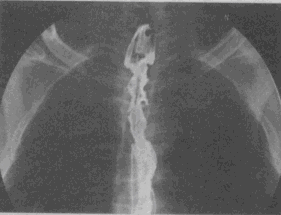

1.男,58歲,進食梗阻感,結合圖像,最可能的診斷為

A.正常食管

B.食管靜脈曲張

C.食管平滑肌瘤

D.食管上段癌

E.食管下段癌

正確答案:D解題思路:食管范圍較長的不規(guī)則充盈缺損,管腔變窄,伴表面有龕影,結合病史為食管癌性病變。